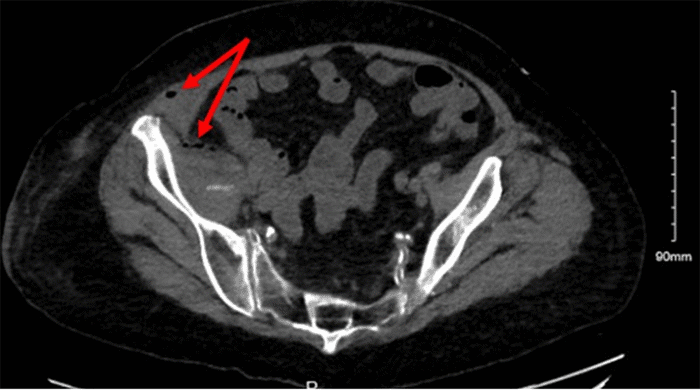

Computed tomography (CT) of the abdomen and pelvis demonstrated inflammation and gas within the right pelvic wall with 5 cm of complex fluid collection (Figure 2), and gas tracking along the psoas and iliacus muscles (Figures 3 and 4), suggestive of septic shock secondary to NSTI. Given the patient’s clinical presentation of septic shock, aggressive management was initiated with intravenous fluid resuscitation, broad-spectrum antibiotics, and reversal of coagulopathy using prothrombin complex concentrate and vitamin K. Subsequently, the patient underwent emergent surgical exploration and debridement of the infected right groin region.

Figure 2. Right Pelvic Wall Inflammation. Published with Permission

CT Abdomen and Pelvis showing fat stranding, gas, and fluid in the right pelvic wall.

Figure 4. Gas and Heterogeneity in Iliacus Muscle. Published with Permission

CT Abdomen and Pelvis showing small bubbles of gas and heterogeneity of the iliacus muscle as well as gas in the right abdominal wall.